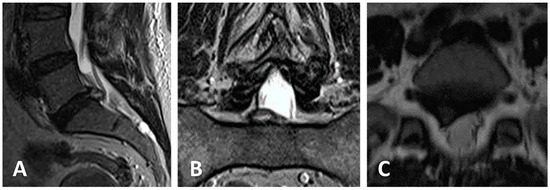

3.3. Clinical Case 1

3.4. Clinical Case 2